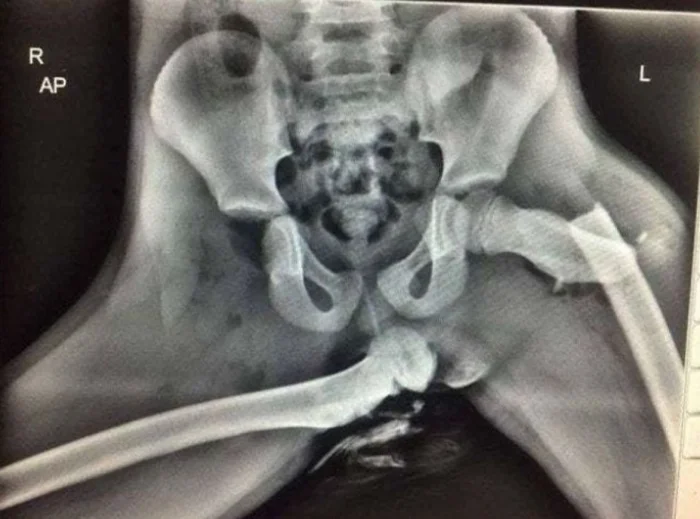

Когда во время аварии ноги оказались на приборной панели